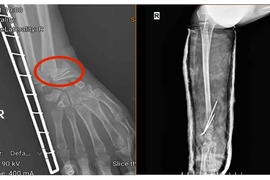

Ứng dụng kỹ thuật C-arm trong phẫu thuật xương gãy không để lại sẹo

Ứng dụng C-arm trong phẫu thuật kết hợp xương đóng vai trò rất quan trọng trong việc tăng độ chính xác, giảm xâm lấn, rút ngắn thời gian phẫu thuật.